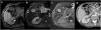

The use of hepatobiliary-specific contrast agents in liver MRI is a crucial diagnostic tool for evaluating liver disease, enabling the detection and characterisation of focal lesions and vascular alterations, as well as the assessment and grading of chronic hepatopathy. Paramagnetic hepatobiliary-specific contrast agents are gadolinium-based, partially taken up by hepatocytes, and excreted via both renal and biliary pathways. There are two linear ionic molecules that are currently commercially available: gadobenic acid (Gd-BOPTA) and gadoxetic acid (Gd-EOB-DTPA). Their main clinical indications include distinguishing and characterising focal liver lesions on healthy liver tissue, diagnosing and staging hepatocellular carcinoma in patients with chronic hepatopathy, and increasing reliability in the detection of hepatic metastases in oncology patients, especially prior to surgery. They are also useful in the evaluation of the biliary tract and in assessing complications of hepatic surgery such as bile leaks.